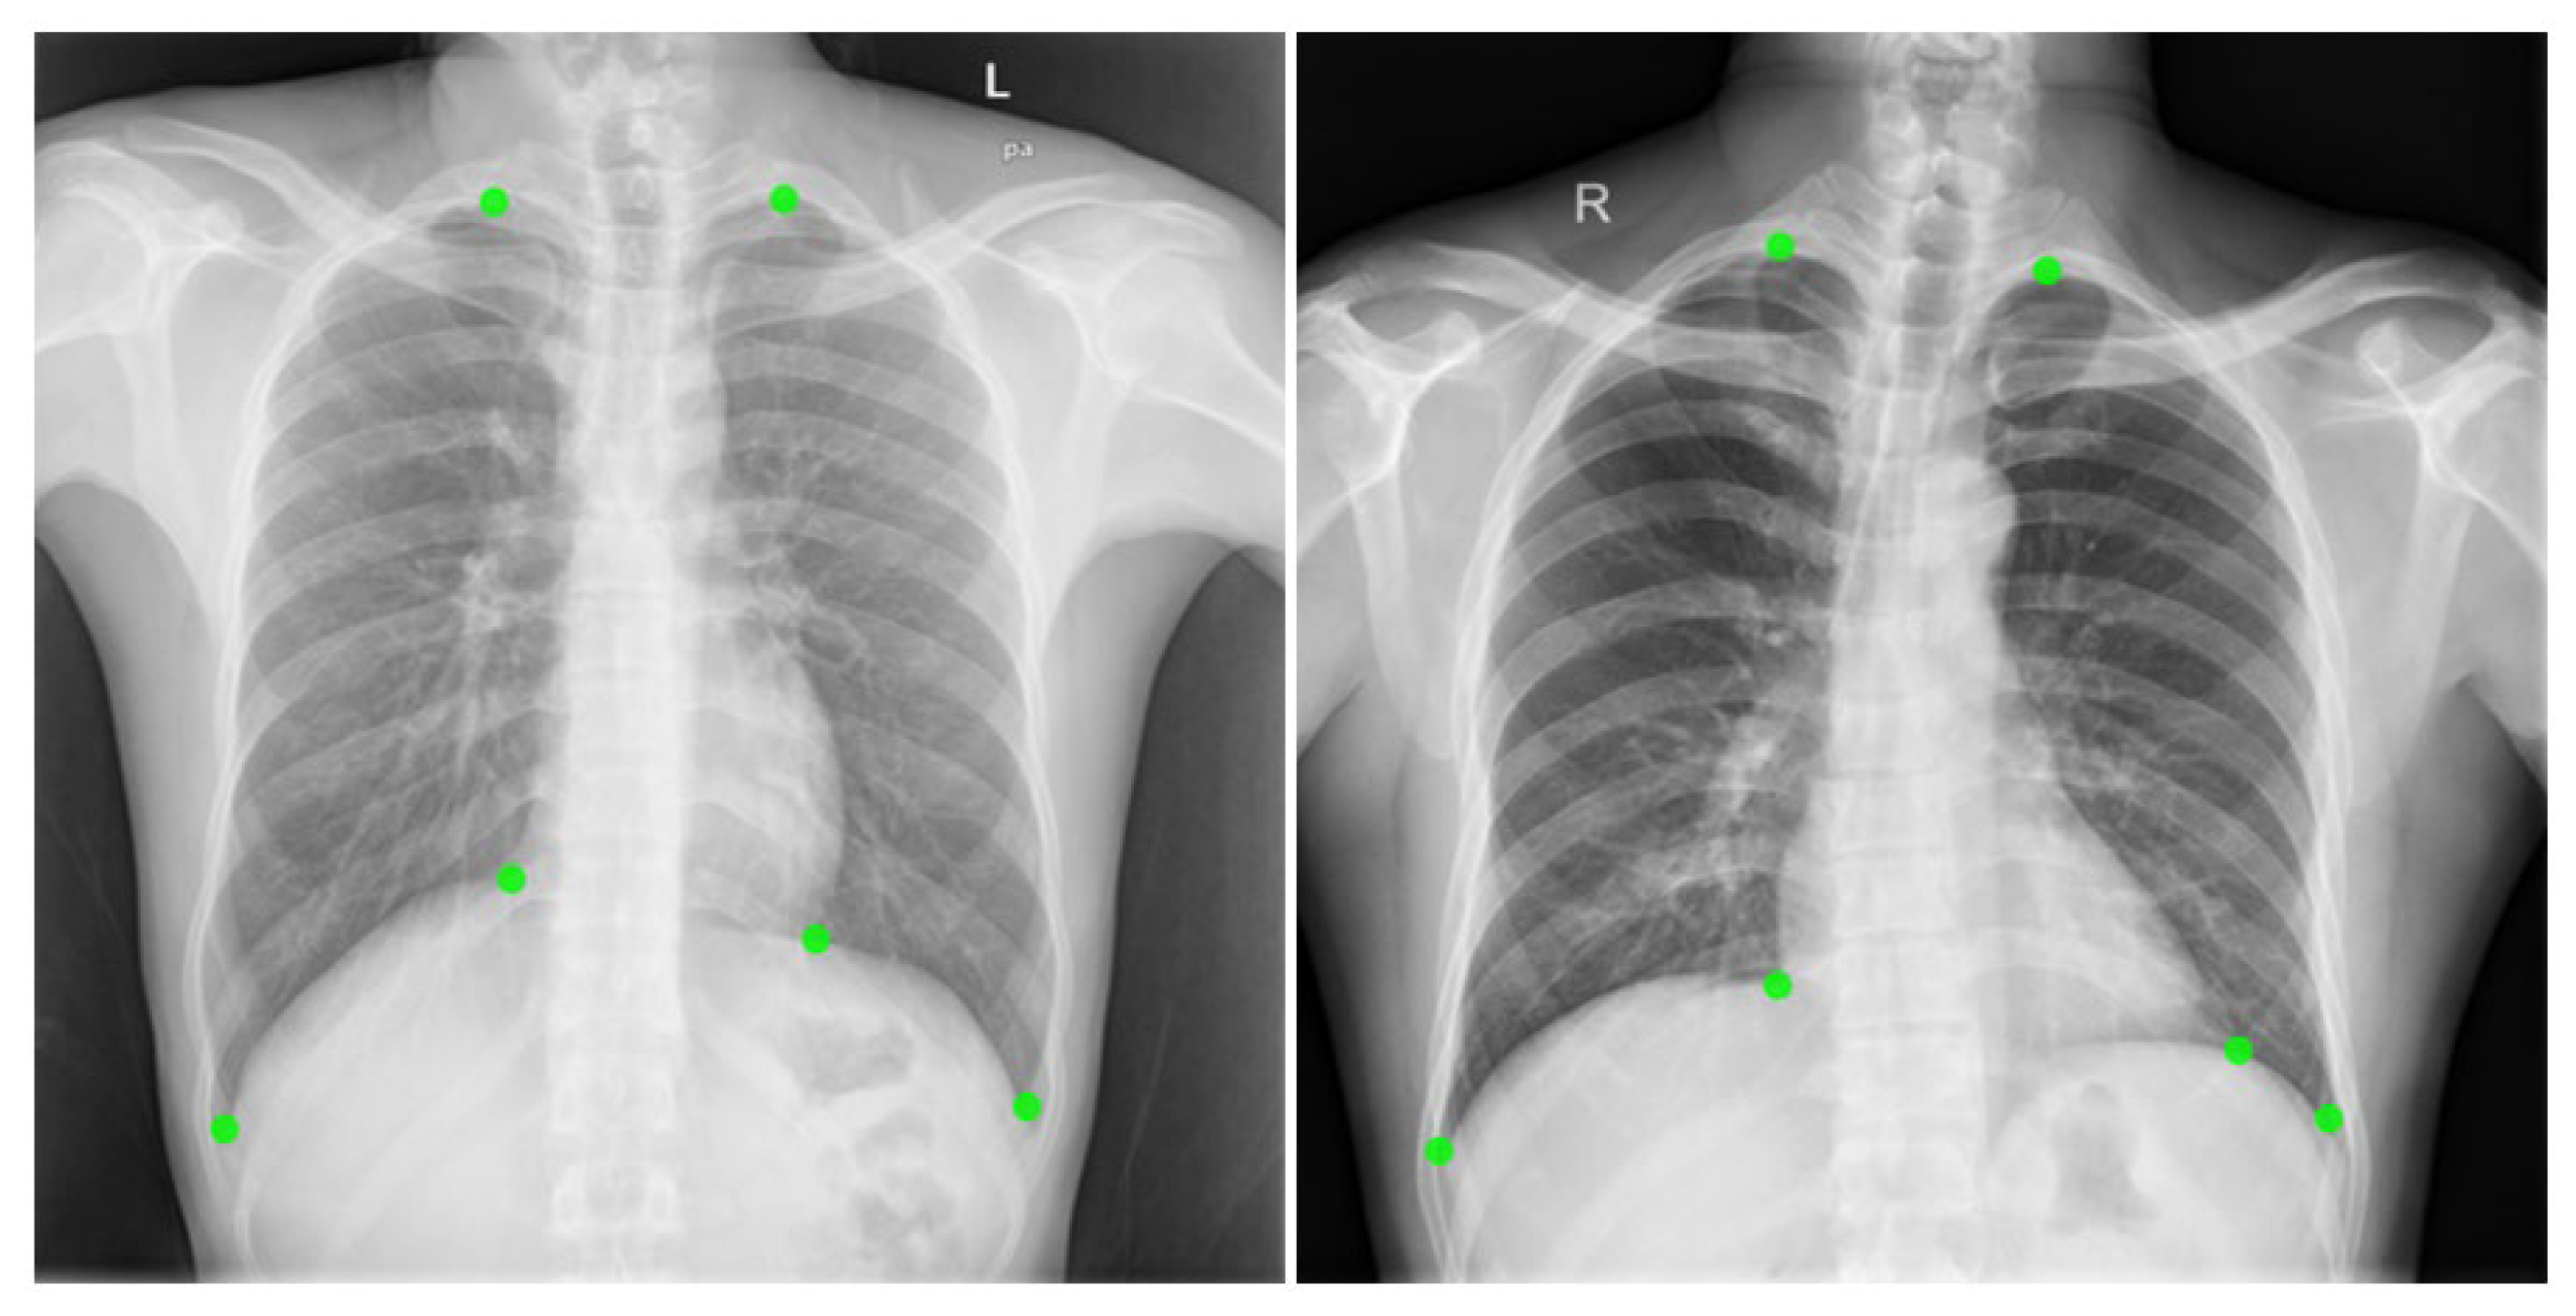

For the experiments, we evaluated the performance of the proposed model using a chest X-ray dataset of 279 images annotated with six pulmonary anatomical landmarks. Figure 1 visualizes the dataset along with the ground-truth placement of each landmark. To examine the effects of the structural constraints—symmetry, ordering, and the GNN-based refinement—we conducted additional experiments using various combinations of these components. These evaluations allowed quantitative verification of how each structural constraint contributes to the stability of the overall landmark configuration.

Figure 1. Visualization of boundary landmarks on chest X-ray images. Green dots denote ground-truth landmark points. L: left, R: right, PA: posterior-anterior view.